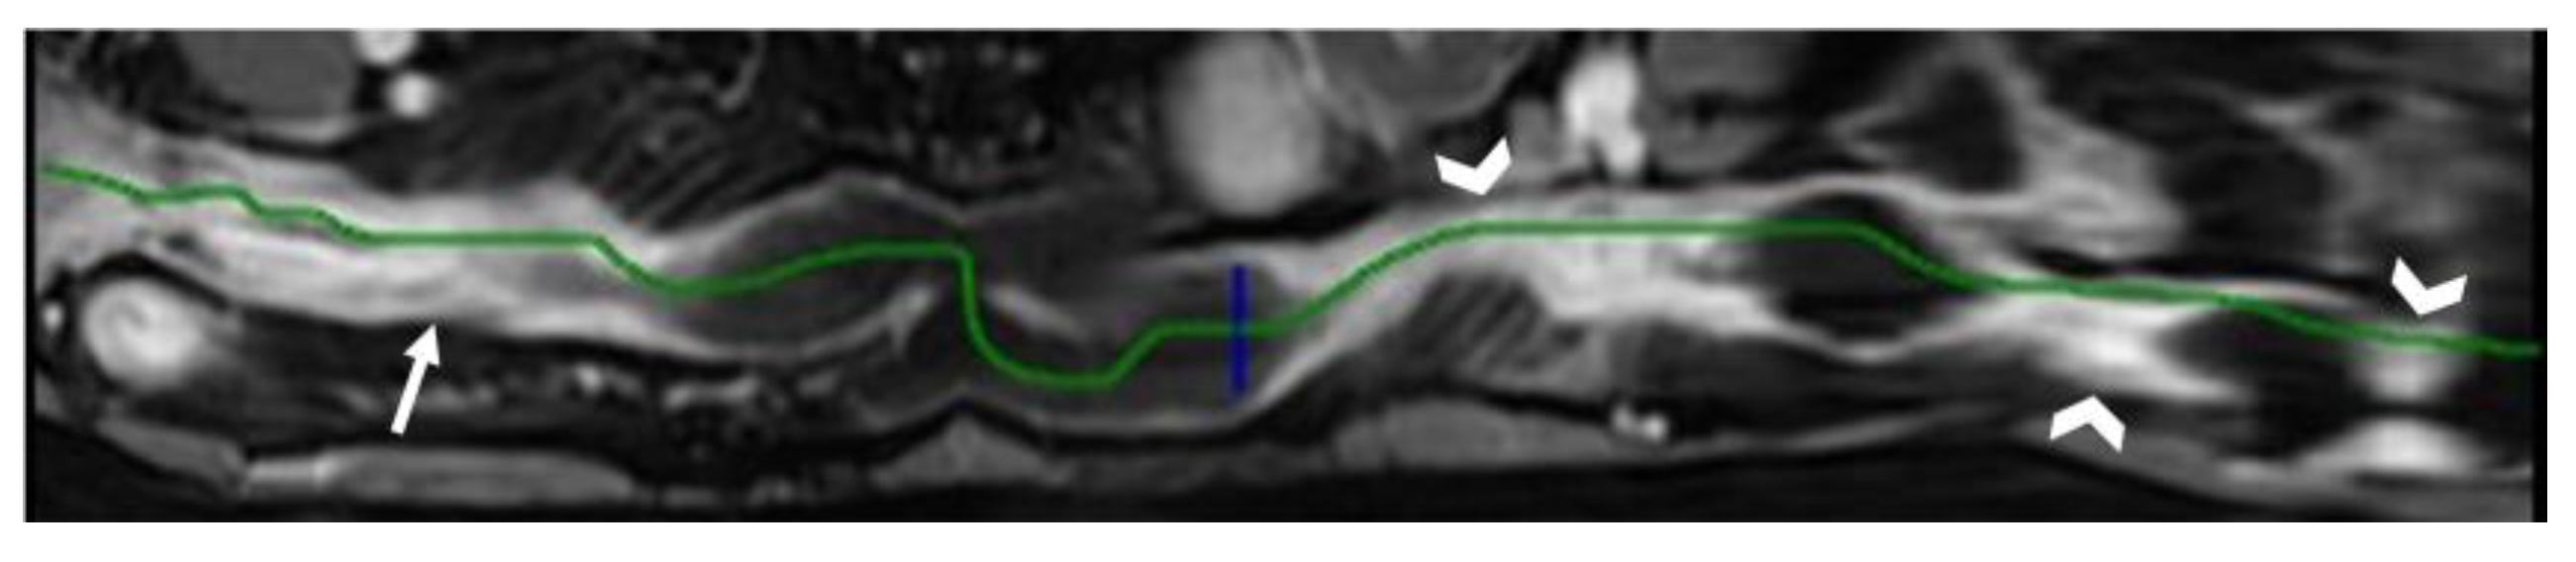

- A normal bowel loop caliber ranges between 2 and 2.5 cm. A bowel lumen is dilated when it has a maximum diameter greater than 2.5–3 cm. The dilation is mild when the upstream lumen is dilated up to 4 cm and severe when it is more than 4 cm (Figure 3) [24]. Pre-stenotic bowel dilatation should always be checked, as it is a sign related to bowel obstruction. Moderate to severe stenosis was determined via double-contrast imaging (conventional barium study) with a sufficient amount of injected air, and stenosis was defined as stenosis in which the lumen was less than one half that of neighboring healthy intestine [25].